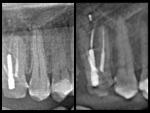

3. Анализ томограммы

- • Горизонтальный срез на границе апикальной трети (рис. 64-66): обнаруживается щелевидная форма и объединение корневых каналов 1.5 зуба в один.

- • Горизонтальный срез в 2 миллиметрах от апекса (рис. 67-68): корневые каналы опять раздваиваются.

| Рис. 64-66 Профильные срезы и 3-D визуализация апикальной трети 1.5 зуба: корневые каналы сливаются |

| Рис. 67-68 Профильные срезы и 3-D визуализация в 2 мм от апекса: корневые каналы расходятся |